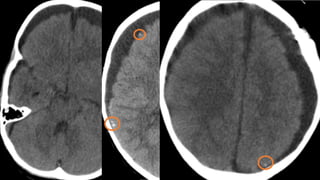

Este documento presenta el caso de un niño de 3 años que sufrió episodios de paresia y alteraciones neurológicas. Exámenes revelaron la presencia de un higroma cerebral que fue drenado. A pesar de una mejoría inicial, el niño continuó presentando síntomas neurológicos intermitentes. Exámenes posteriores identificaron una rara vasculopatía que afecta vasos cerebrales y otros órganos, con un pronóstico grave.